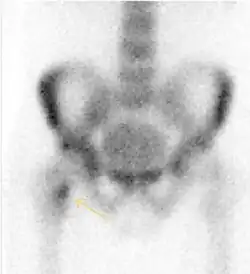

MRI has been shown to have 100% sensitivity and specificity in prospective studies of occult hip fractures. These fractures were diagnosed by bone marrow edema and a low signal fracture line, mainly on T1 or T2 weighted images (Figure 10).[1]

Figure 10:

Stress femoral neck fracture in a young athlete barely visible in X-ray film as a sclerotic line (arrow)[1] -

In this case, Tc 99 scintigraphy shows a band of uptake[1] -

Furthermore, T1 (left) and DP fat saturated (right) weighted MR images showed the fracture line and a pattern of edema.[1]

Nuclear Medicine

Bone scanning in people with hip pain can be complementary to other imaging studies, mainly in indeterminate bone lesions to clarify whether it is an active lesion with abnormal radiotracer accumulation. Nevertheless, MRI has replaced scintigraphy in the diagnosis of most of these conditions. An example is stress or insufficiency fractures: increased uptake is usually present in around 80% of fractures within 24 h, and 95% of fractures reveal activity by 72 h following trauma, showing an overall sensitivity of 93% and specificity of 95%. MRI is superior to bone scans in terms of sensitivity (99%-100%) and specificity (100%). Moreover, a bone scan does not provide detailed anatomical location of the fracture, and further imaging is usually required.[1]